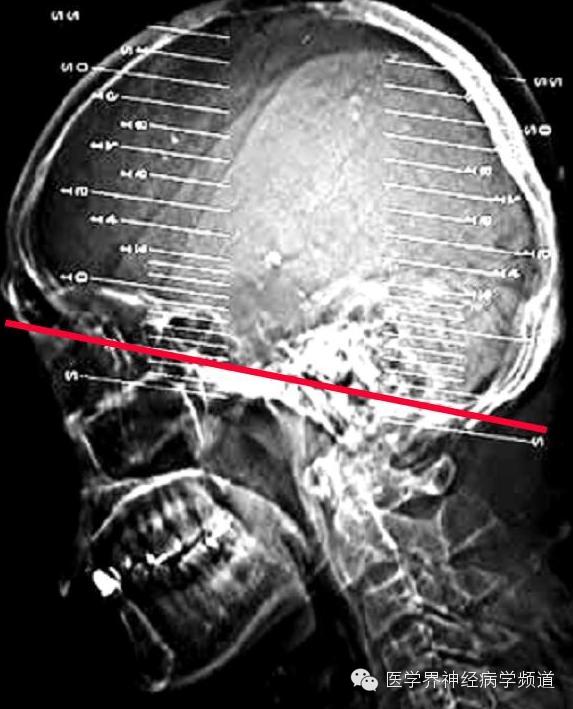

神经影像CT读片step by step